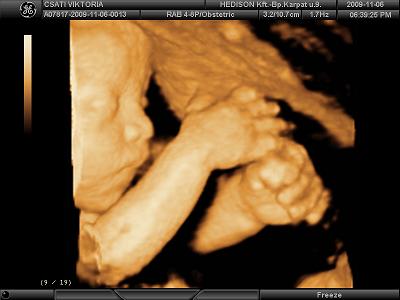

Töltök fel képeket. nekünk csak fekete-fehér van, de legközelebb már kérek színeset, mert megirigyeltem tőletek :)

nagyon bújkált a babánk, szinte végig a hátát láttuk. azért sikerült lefotózni a pofikáját is, de még nagyon ufós :)